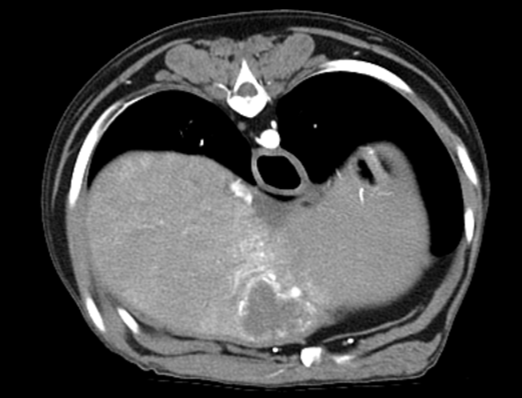

160ch CT

160 slice CT는 빠른 속도로 환자의 마취 시간을 줄이며(5분 이내) 정확한 진단에 도움을 줍니다. 또한 심장 등의 장기를 평가함에 있어 기존 64채널 CT에 비해

우수한 해상도의 영상을 획득 가능합니다.

160 slice CT는 국내 동물병원에서 최상급 촬영장비(Toshiba Acquilion Prime)에 해당하며 conventional CT 촬영 이외에도 추가적인 body perfusion,

dual energy 등도 가능합니다.

160채널 CT는 고화질 영상으로 숨어있는 비정상적인 문제점들을 찾아내어 진단 및 치료에 도움을 주고 있습니다.

Early arterial phase

Late arterial phase

Portal phase

Delayed phase

03복부 CT

· 간, 비장의 종양을 포함한 실질 변화 및 혈관기형(PSS)의 평가

· 소화기, 비뇨기 실질장기의 평가(종양, 이물, 염증 등)